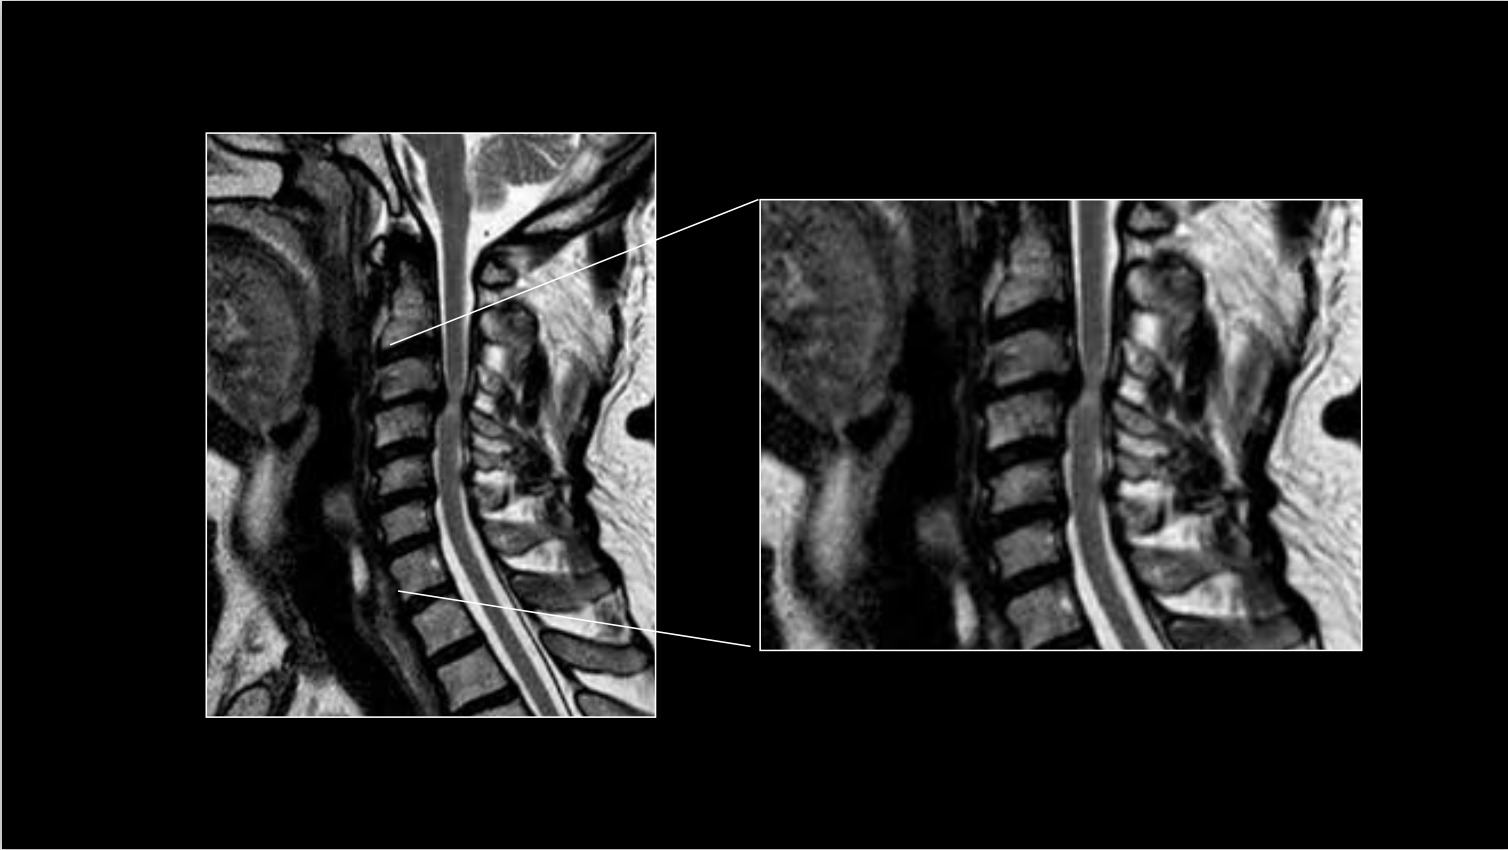

Hernia discal cervical

Estenosis de canal cervical

Mismos mecanismos que la estenosis lumbar pero en este segmento, la estrechez del canal, no comprime solo los nervios si no también la médula espinal. La compresión de la médula espinal puede general torpeza, rigidez, debilidad y dolor en los brazos y las piernas.